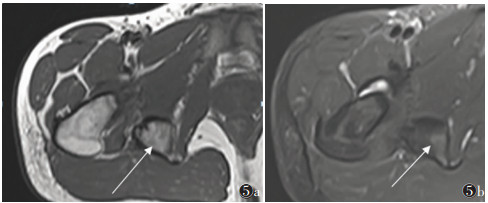

晚期病变21例,X线(21例)、CT(15例)、MRI(11例)及SPECT/CT(15例)阳性率均为100.0%。X线或CT表现为软组织内团状密度增高影,边界清晰,其中9例与相邻骨骼相连,与皮质分界不清,但髓腔不受累。MRI表现为肿块内广泛的T1WI高信号、T2WI低信号(骨化),9例病灶内含T1WI等信号、T2WI高信号、STIR低信号影(脂肪)(图 5)。SEPCT/CT显像15例,其中3例病灶中央及周围均未见显像剂摄取(图 6);6例病灶中央显像剂不均匀摄取(图 7);6例病灶周围显像剂不均匀摄取(图 8)。

| 图 5 男,16岁,右侧髋关节骨化性肌炎(晚期) 图 5a,5b 分别为MRI T1WI横轴位、T2WI STIR横轴位图像,显示右侧髋关节后侧骨化肿块,其内含脂肪信号(箭头) |

3.3 晚期外伤后5~6个月,肿块开始收缩,周围水肿减轻乃至消失,此期影像学诊断相对容易。X线或CT表现为边界清晰的团块状骨化,可与相邻骨骼相连,与皮质分界不清,但髓腔不受累;MRI表现为肿块内广泛的双低信号,其内可含脂肪信号。但本研究中晚期患者的SPECT/CT特征不一致,可表现为病灶完全无显像剂摄取或病灶中央显像剂高摄取而周围无摄取,也可能表现为中央无显像剂摄取而周围高摄取。提示骨化性肌炎的骨化可能是一个复杂的过程,具体机制有待进一步研究。